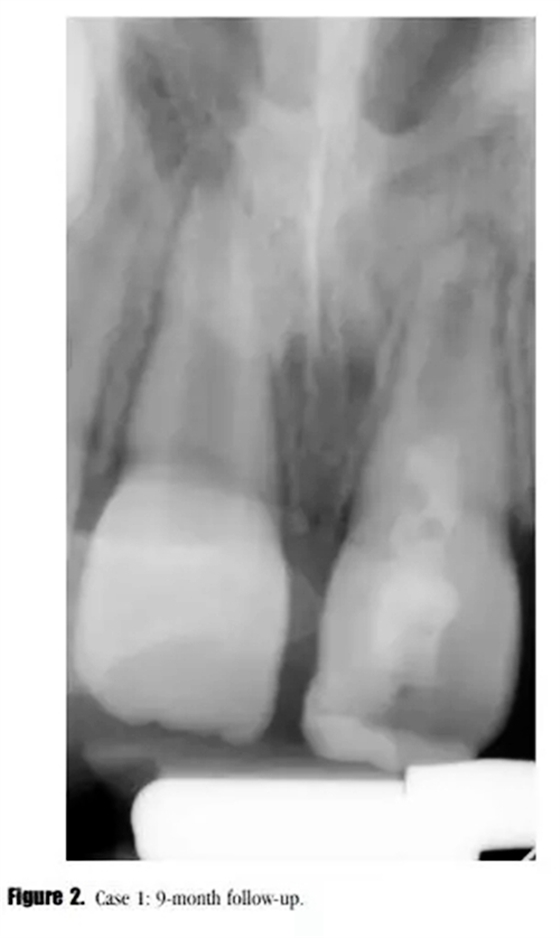

在3,6,9個月的隨后跟蹤隨訪中,患者完全沒有癥狀。與鄰牙和對側(cè)牙對比,21的叩診、捫診以及牙周袋深度都在正常范圍內(nèi)。對于牙髓溫度測試沒有反應。影像學評估顯示,根尖區(qū)低密度透射影像范圍減小,牙根發(fā)育為I型(按照Chueh等人的研究)(圖2),

在第12個月的評估中,叩診與捫診又輕微不適。在臨床牙冠上未發(fā)現(xiàn)充填材料與牙體的縫隙以及隱裂線,探診深度正常。我們采用了一種細菌加強型封閉劑來預防再感染。影像學評估顯示,根尖周投射影增大、牙根停止發(fā)育,以及近中根管內(nèi)壁的輕微吸收。(圖3)